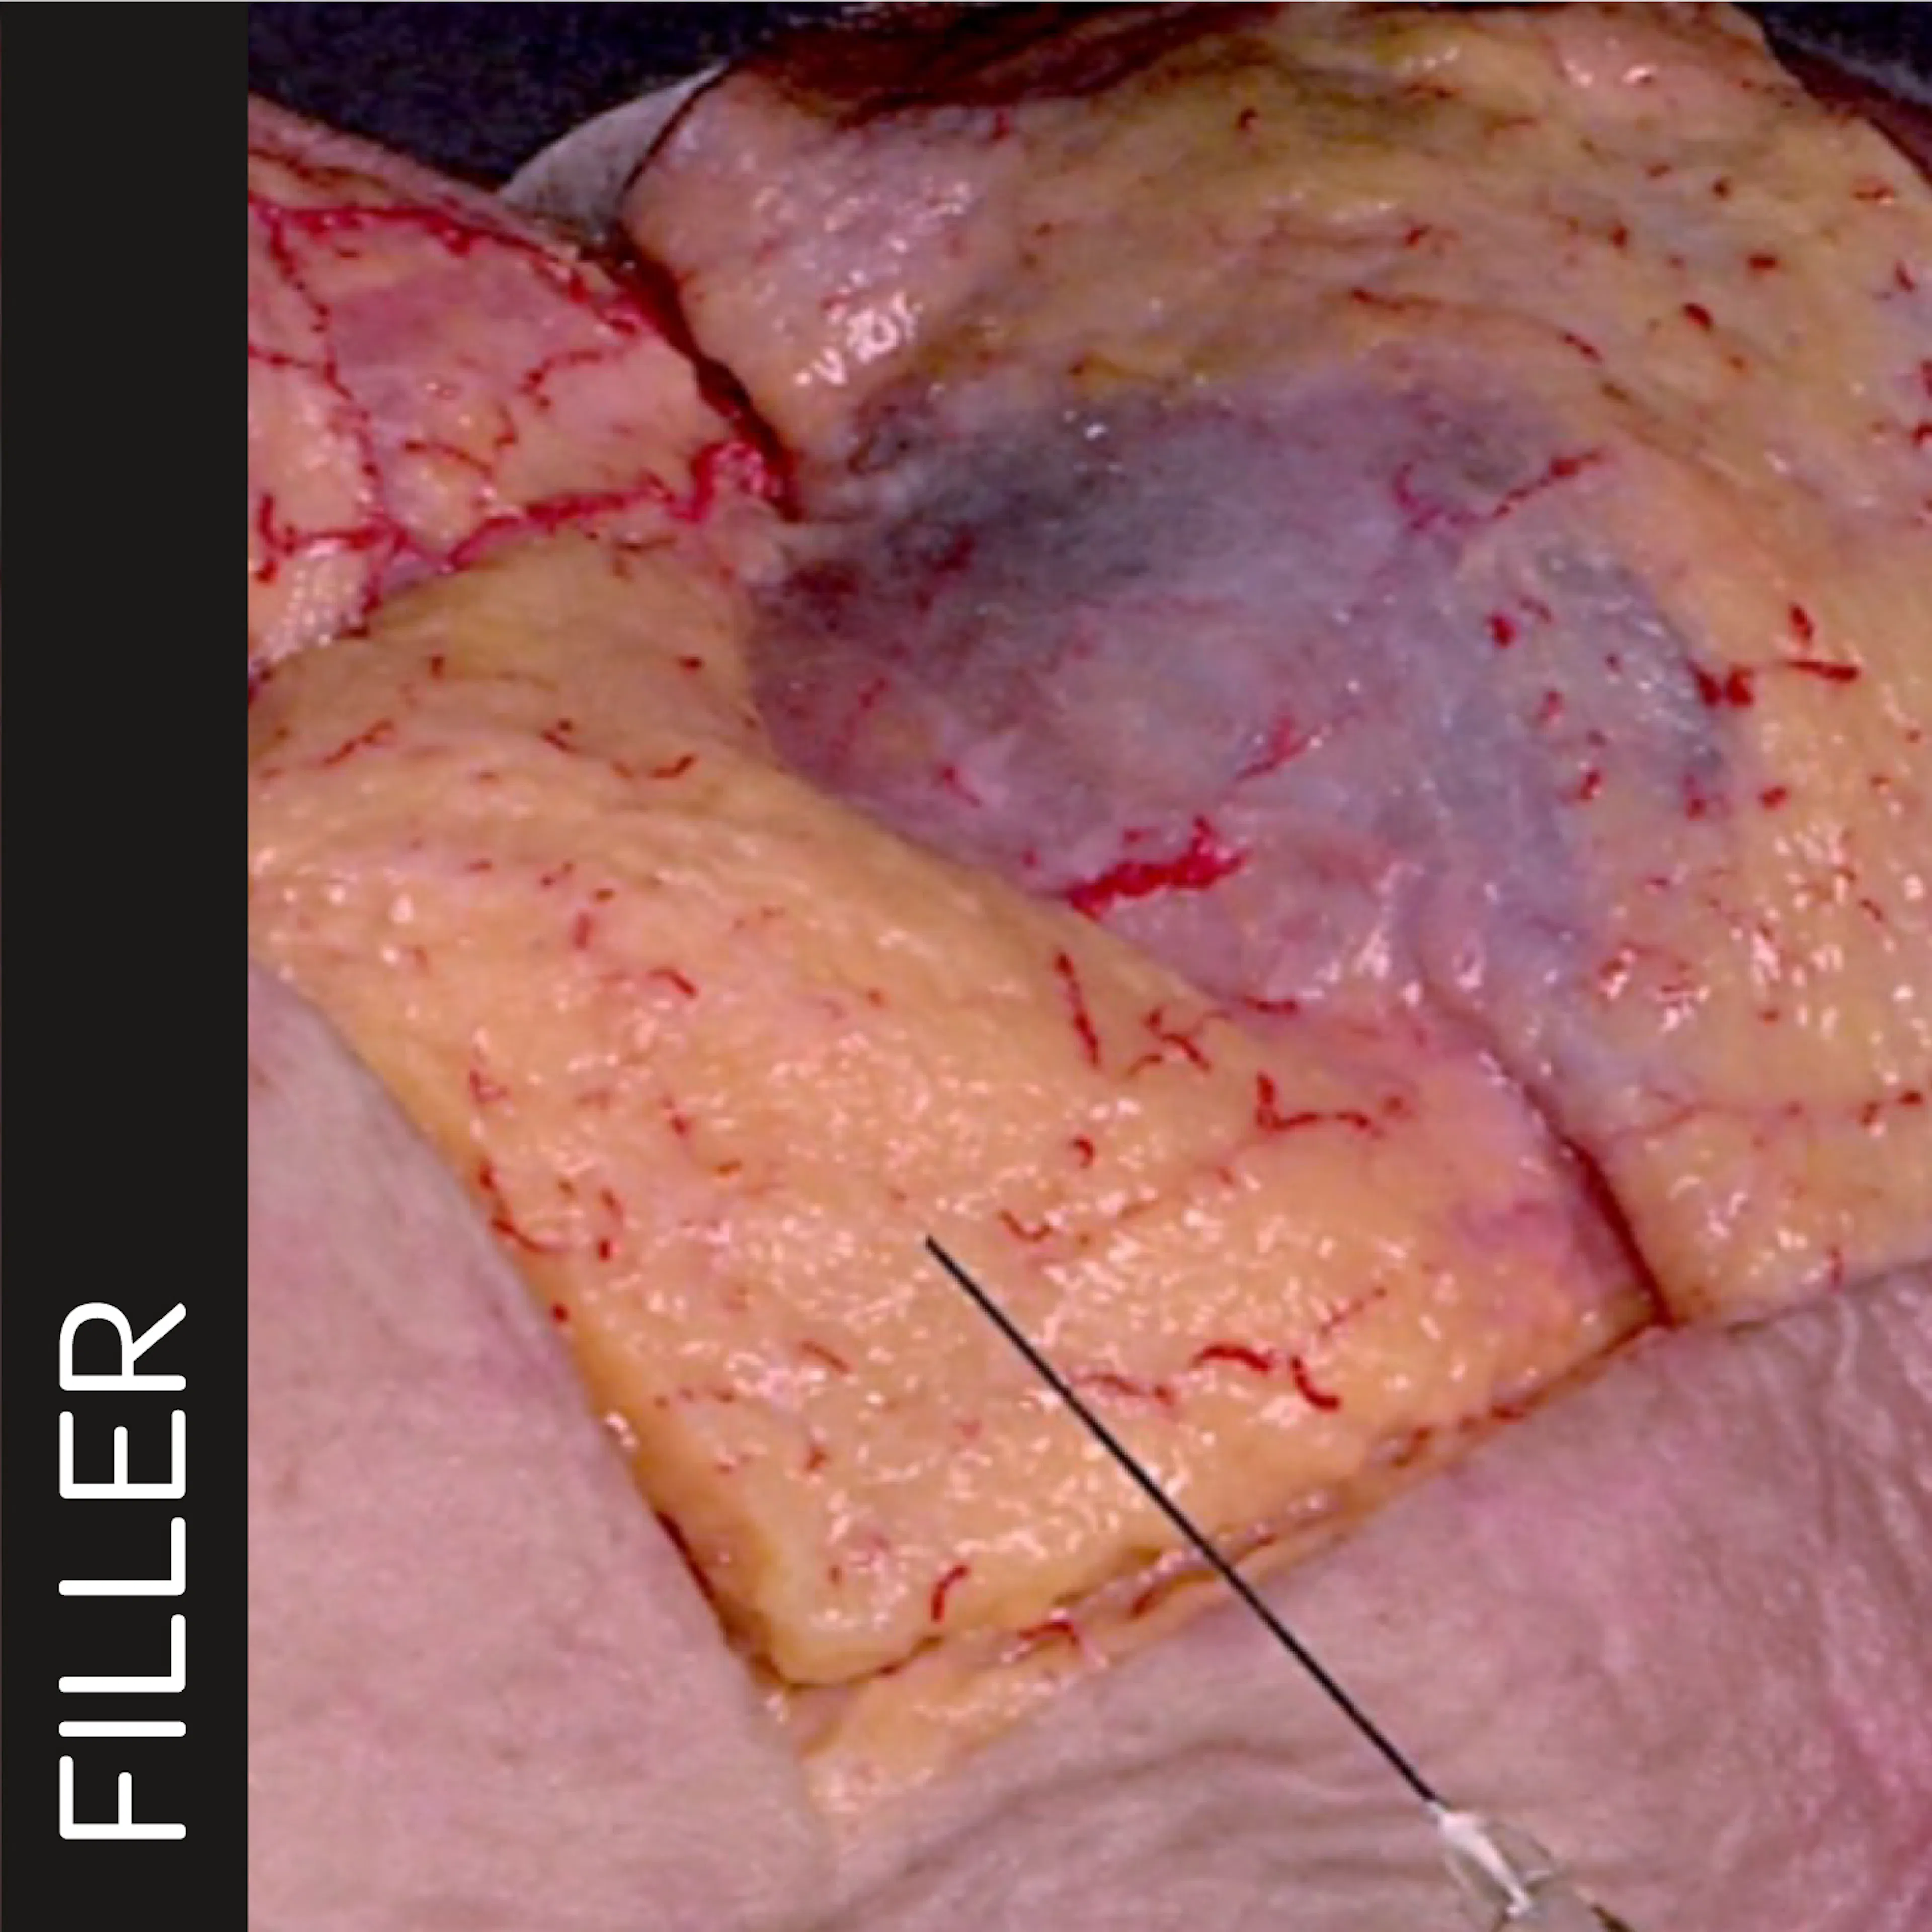

Anterior Midface Volumization: Superficial Cannula Technique

Treatment type: Soft Tissue Fillers

Facial region: Nasolabial fold

Approach: Cannula Injection Technique

Course type: Injection simulation on a human body donor performed by Prof. Sebastian Cotofana

Traditionally, the medial midface is a deep-injection-region. However, recent advancement in soft tissue filler rheology, have allowed for superficial product deposition targeting the superficial fat compartments. In this video, you will see and learn about what to take care of when performing this subdermal cannula-based injection technique.